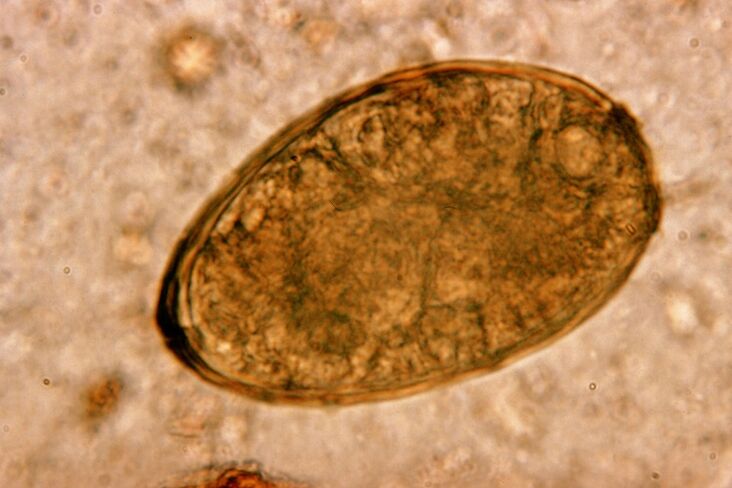

Toxocara ug pulmonary fluke

Ang labing peligro sa sistema sa respiratory mao ang mga flatworms, sa partikular nga mga flukes ug mga tonocaras. Ang pagkalakip sa baga, hinungdan sa mga parasonimiasissis ug toxocariasis - grabe nga mga sakit nga giubanan sa pagkaguba sa bagyo sa baga ug usa ka progresibo nga proseso sa panghubag.

Ang pagsulod sa mga flatworm sa baga sa bata hinungdan nga siya mag-ubo. Kung wala pa matino, ang proseso sa panghubag nag-uswag ug mosulod sa usa ka entablado nga giubanan sa pagporma sa uhog. Ang pagsulud sa sputum mahimong adunay dugo. Ang nakapaalarma nga pagpadayag kinahanglan magpugos sa mga ginikanan nga dali nga mokonsulta sa usa ka makatakod nga doktor sa sakit.

Ang fluke nagpuyo sa baga nga nagtinagurha, nga nagporma cysts sa bronchi. Ang infestation mahitabo sa pagkaon sa mga crab ug crayfish nga nataptan sa parasito. Kas-a sa gastrointestinal tract, ang pulmonary fleting mitutok sa peritoneum ug nakaabut sa baga pinaagi sa diaphragm, hinungdan sa kanunay nga ubas sa pasyente.

Ang gamay nga helminth nga pulmonary fluke, nga sakop sa klase sa mga trematodes, "espesyalista" sa parasitizing nga piho sa baga. Kini ang hinungdan sa labi ka labi ka grabe nga mga problema sa sistema sa respiratory kaysa mga roundworms, pananglitan.

Sa lugar sa pag-localize niini, ang mga infiltrate makita ug ang mga hemorrhage naugmad, ingon nga sangputanan nga makita ang mga cavies nga puno sa pagkadunot nga mga metabolite sa mga ulod, patay nga mga parasito ug baga nga tisyu. Ang kadaut gikan sa pulmonary fluke labi nga nagkagrabe sa kamatuoran nga kini usa ka lay-atay ug puy-anan sa lawas sa host hangtod sa 20 ka tuig.